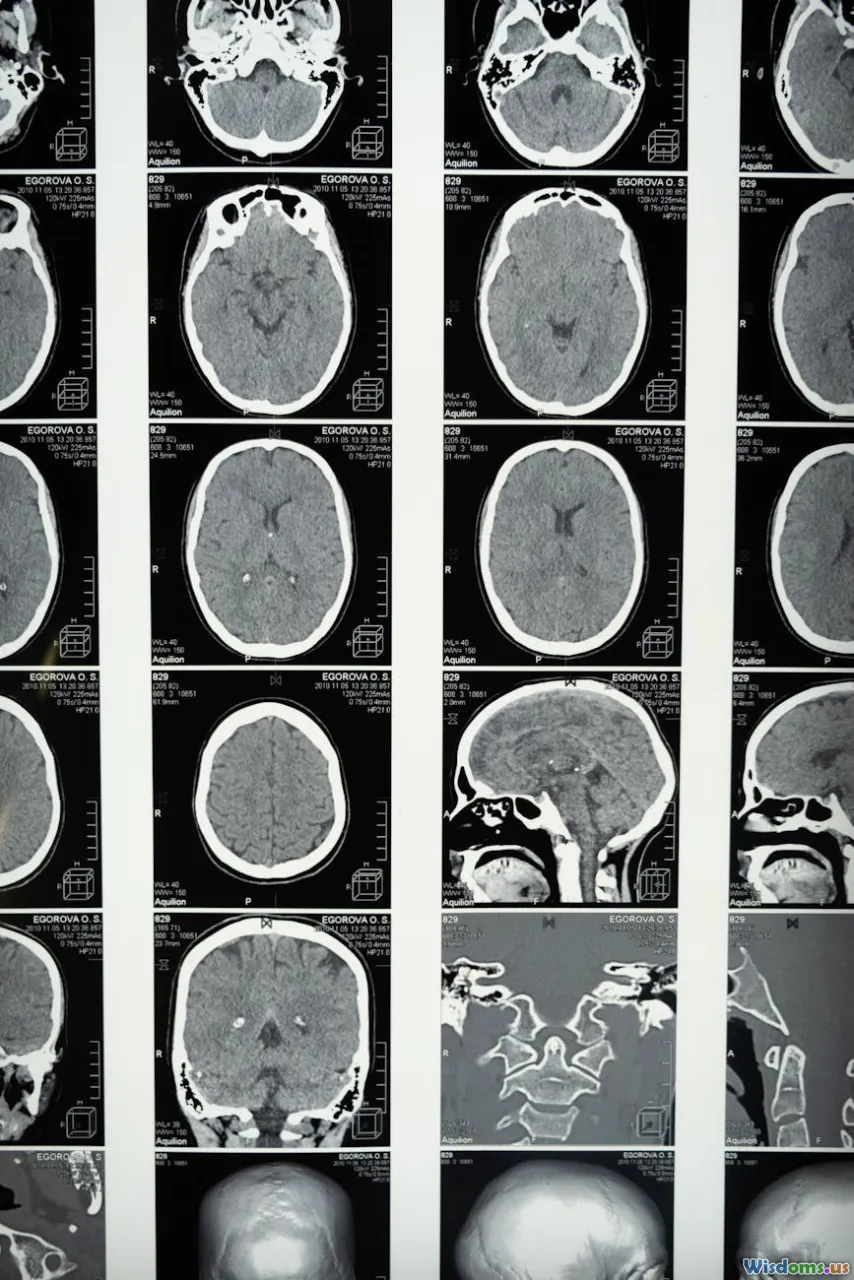

• Safety and monitoring: Amyloid-related imaging abnormalities (ARIA)—brain edema (ARIA-E) or small hemorrhages (ARIA-H)—occurred in a notable minority of patients, particularly those with an APOE ε4 genotype. Most ARIA is asymptomatic and detected via MRI, but some people develop headaches, confusion, or visual symptoms. These therapies require regular MRIs and infusion-center access.